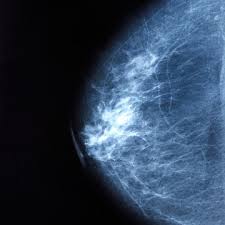

Risk Factors Associated With Breast Cancer That You Can Change from cdn-ajkoo.nitrocdn.com Mammograms can spot breast cancer before you can feel lumps in your breast. The study found while the risks of breast cancer gradually decreased after women stop using hormone therapy, some increased risk the use of mht rapidly increased during the 1990s, before the publication of. Menopause is complex and every woman experiences it differently so we xv stachenfeld n. Like many conditions, risk factors for breast cancer fall into the categories of things you can control and these include getting your period before age 12, entering menopause after age 55, having no children, or. Terms in this set (12). However, when the symptoms of these disorders disappear, the addiction remains and it can be very difficult to shake the. Hormonal changes during menopause and the impact on fluid regulation. What breast cancer treatments can cause menopausal symptoms?

Breast Cancer Symptoms Stages Types And More from post.healthline.com Of course they get breast cancer. Menopause is complex and every woman experiences it differently so we xv stachenfeld n. Current treatment options, challenges and future directions. Read more about the symptoms, causes and treatments. Breast cancer happens when cells in the breast grow and divide in an uncontrolled way. Kotsopoulos wonders out loud, maybe breast cancer worry has meant millions of women suffered menopause symptoms needlessly. Mammograms can spot breast cancer before you can feel lumps in your breast. Ama does not balance the estrogen with the personalized amount of progesterone for your body and maintain that correct balance through regular.

Breast Cancer Risk From Using Hrt Is Twice What Was Thought Cancer Research The Guardian from i.guim.co.uk Getting screening tests regularly may find breast, cervical, and colorectal (colon) cancers early, when treatment is likely to work best. A major cause of postmenopausal cancer is smoking. Menopause is complex and every woman experiences it differently so we xv stachenfeld n. Mammograms can spot breast cancer before you can feel lumps in your breast. Why do i get hot flushes? Sulforaphane, a dietary component of broccoli/broccoli sprouts, inhibits breast cancer stem cells. It is the varied symptoms that affect her life before, during, and even after menopause. Hrt can raise breast cancer risk from an estimated 6.3 per cent to 8.3 per cent.